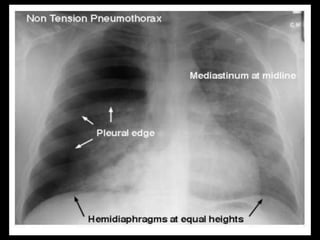

Chest X-ray :-

• Hyper translucency between the lung & thoracic cage.

• Razor sharp border of the collapsed lung.

• Shifting of mediastinum on the opposite side of injury.

RADIOLOGICAL FINDINGS Chest X-ray:- • Hyper translucency between the lung & thoracic cage. • Razor sharp border of the collapsed lung. • Shifting of mediastinum on the opposite side of injury. Chest CT scan :- • Intrapleural gas along with loculated pneumothoraces. • Pleural effusion, pneumothorax. Chest Ultrasound :- • Smooth horizontal echogenic lines are seen above and below the pleural lines. • Absence of lung sliding and B - lines.